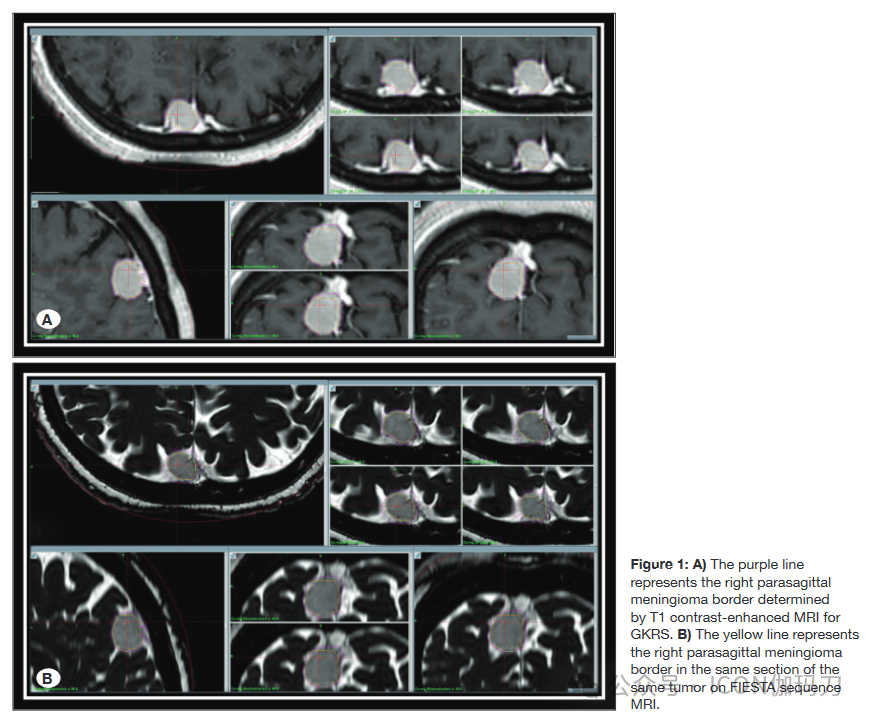

回顾了2020年1月至2022年6月在Pamukkale大学接受GKRS (Leksell伽玛刀®Perfexion™)治疗的102例脑膜瘤患者的MRI图像。按照建议使用T1+C MRI序列进行GKRS定位。此外,FIESTA MRI检查使用指定的参数(重复时间/回时间,6,7/2,8 msec;FA 60°;320 x256矩阵;厚,2mm;相交间隙,0 mm;视240X240 mm)。先前接受过手术或其他治疗(如放疗)的患者被排除在研究之外,因为他们的纳入可能会损害评估的MRI图像的评估。因此,我们回顾性地回顾了54例首次行GKRS的单发脑膜瘤患者的资料。将患者分为两组:1组为伴静脉窦的脑膜瘤(Sindou I-VI型)(35例),2组为无静脉窦侵的脑膜瘤。由于硬脑膜静脉窦的高且均匀的对比增强可能显示与邻近脑膜瘤相似,从而使靶体积增大。因此,我们决定单独对脑膜瘤合并静脉窦侵进行研究。此外,我们还检查了人口统计学数据、肿瘤体积(T1+C和FIESTA MRI序列)和肿瘤的解剖位置,如图1和2所示。

2:A)紫色线代表GKRS的T1增强MRI确定的右侧小脑脑膜瘤边界。B)黄线为FIESTA序列MRI同一肿瘤同一层面右脑脑膜瘤边界。